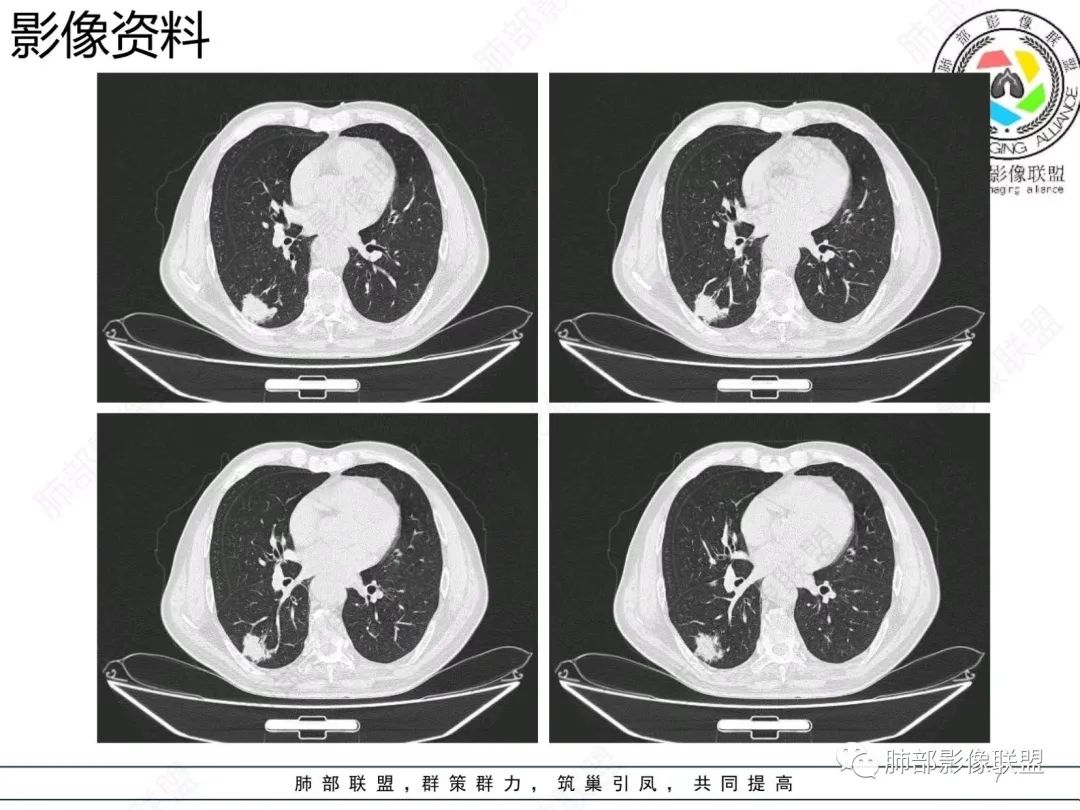

【病例】胸膜下的混合密度结节—良恶之争

尘缘:

结节型粘液腺癌,具有血管弯,支气管截断,磨玻璃边界清楚等恶性征象,同时磨玻璃内部较糊,似清非清,不符合普通腺癌附壁生长特点,更像局限的粘液成分。收缩力不强,胸膜局部微积液,内部小空洞(考虑局部粘液排除形成),所以考虑结节型粘液腺癌。

这个结节型粘液腺癌还是比较典型的

区别1:结节期(影像说结节型)粘液腺癌,粘液成分还大多数局限于粘液腺癌细胞的胞浆中,没有飘出去,所以粘液密度不明显,周围的磨玻璃成分大多数还是分散于肺泡壁上的粘液腺癌细胞,所以边界相对较清楚(时间越晚,飘出去的粘液越多,边界就会越不清楚了),因为胞浆中的粘液成分显得较糊,有点似清非清。而普通腺癌附壁生长的腺癌细胞胞浆中没有粘液,所以非常清楚。

区别2:粘液腺癌的MGGN收缩力不强,普通腺癌的MGGN收缩力明显。

粘液腺癌CT表现:

1.结节型肺粘液腺癌以中老年女性多见,单发,发病部位常位于两下肺胸膜下(肺外周带)。

2.多数病灶具备典型恶性肿瘤征象,但是不典型者仍不少见。可有分叶和棘状突起,但较少出现典型毛刺征。强化程度不如一般的腺癌病灶那么显著。

3.病灶常呈圆形或不规则形,实性结节略多于混合磨玻璃结节,少见于纯磨玻璃结节;或囊实性结节影或肿块,密度混杂,部分可出现钙化;病灶边界可清楚,也可模糊,须与炎性结节鉴别;周围可有类圆形磨玻璃密度卫星灶;表现为实性结节病灶,收缩力可能表现不明显,较少胸膜凹陷或血管集聚,须与良性结节鉴别。

4.原发性肺粘液腺癌侵袭力相对较低,发展慢;病灶较少破坏支气管及血管,可表现为血管造影征及空气支气管征。较少胸膜侵犯,也较少肺门纵隔淋巴结转移。